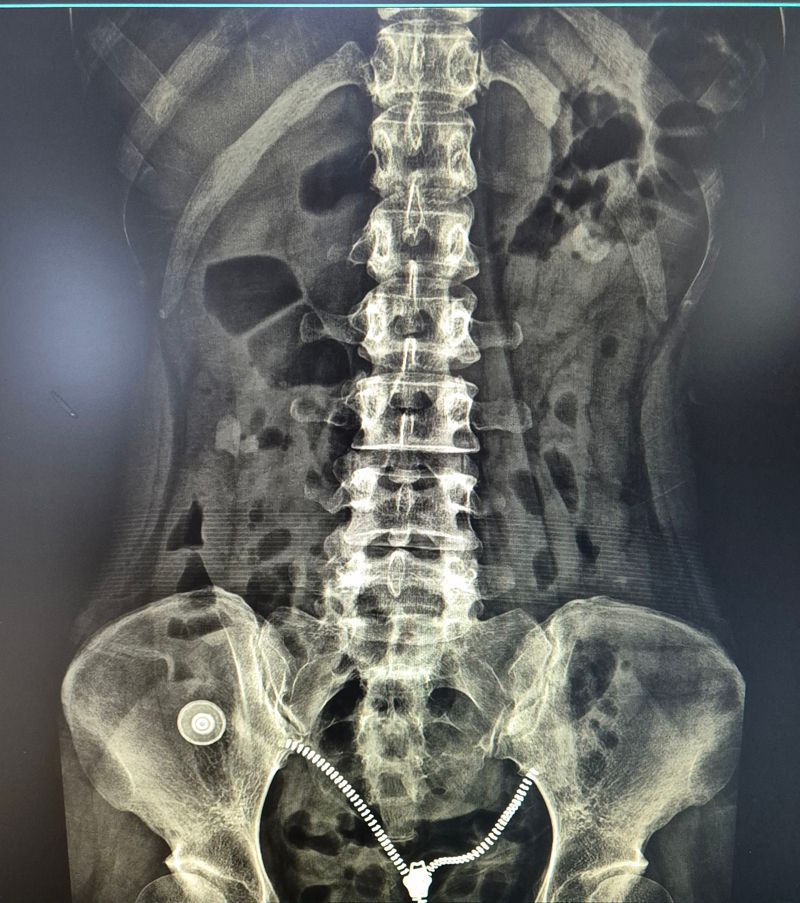

허리 디스크 심한 편인가요? (사진有)

허리에 시큰거리는 통증이 생겨서 병원 갔더니 엑스레이 찍더라구요

요추5번 천추1번 사이(?)라고 들은 것 같은데;

암튼 꼬리뼈로 이어지는 디스크가 좁아진 거라며 디스크라는데

엑스레이상에서는 디스크를 판단할 수 없습니다. 예측은 할 수 있습니다. 엑스레이상 볼때는

등이랑 허리 부분이 뻣뻣할것으로 보이며 (만곡이 거의 없이 일자 허리로 되어 있는 것으로 유추)

허리뼈 5번이랑 꼬리뼈 1번 척추 간격이 상당히 좁습니다. 간격이 좁게 되면 허리가 뒤로 재끼거나

질문자분의 엑스레이 사진을 보았을때 일단 허리뼈 5번이랑 꼬리뼈 1번 척추뼈 사이 공간이 조금 좁기는 하지만 정확한 상태를 확인하고 싶으시다면 역시 MRI를 찍어보시는게 좋을것 같습니다.

요추5번과 천추1번사이가 많이 좁아져있습니다. 좁아져있는 경우는 단순히 좁은것뿐만아니라 오랜기간에 허리긴장도가 높은상태로 유지되어있었기때문에 그부분도 상당히 중요합니다. 허리를 숙이거나 뒤로꺾는동작은 현재 근육상태가 좋지않을가능성이 높기때문에 오히려 관절에 무리를 줄수있습니다. 디스크가 어느방향으로 얼마나 나와있는지는 mri를 찍어야 더 정확하게 알수있으나 공간이 좁아진것으로봐서 디스크는 확실히있습니다. 다만 이 디스크가 뒤로빠진것인지 옆으로빠진것인지 좌측인지 우측인지를 알기위해 mri가필요한것입니다. 일단 비수술적으로 접근한다면 꾸준한 코어운동이 필요합니다. 코어운동으로 허리의 근육을 잘컨트롤할수있을때는 굽히거나 숙이는동작도 허리에 무리없이 하는경우가 많습니다. 하지만 지금은 최대한 안하시는게 맞습니다. 고로 재활전문가와 함께 코어운동을 꾸준히 하시는것이 좋고 그 전에 먼저 시술이나 수술이 필요한경우인지 아닌지 mri를 찍어보시는것이 우선입니다. 수술이나 시술을 하지않고 재활만으로 가능한 단계인지 시술 수술을하고나서 재활운동을 해야하는단계인지를 먼저 상태를 보셔야합니다.